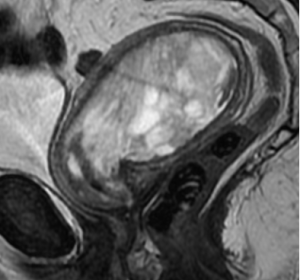

Рис. 1 Карциносаркома на МРТ органов малого таза